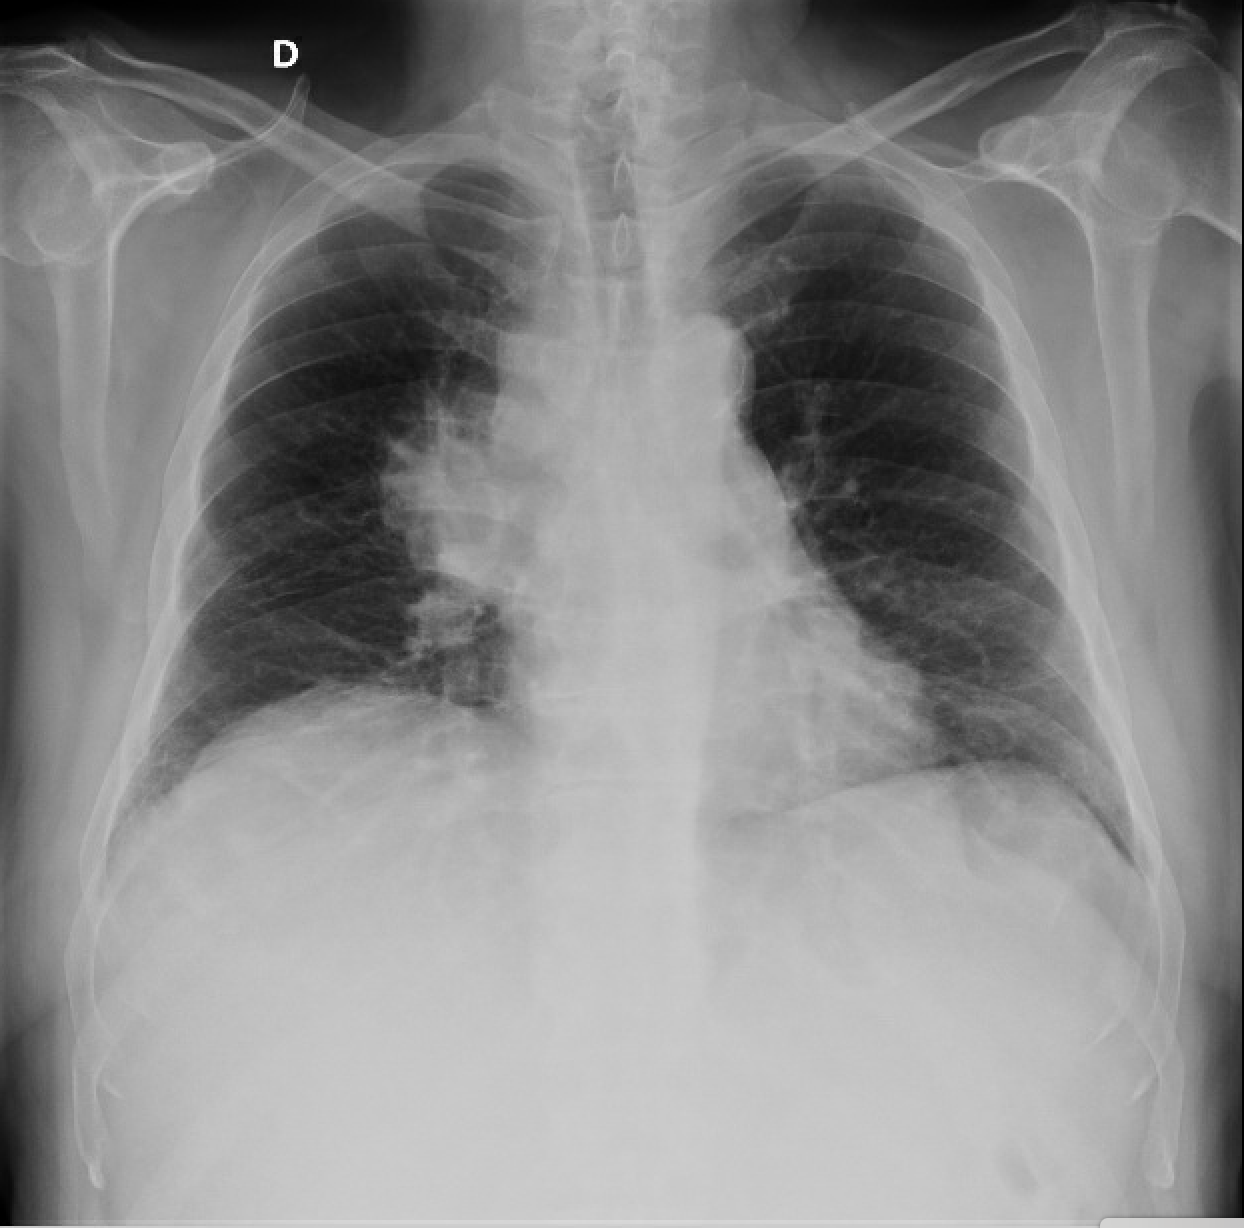

También se realiza radiografía de tórax donde se aprecia masa en región hiliar derecha.

Impresiona de tumor primario de origen pulmonar con metástasis a nivel hepático.